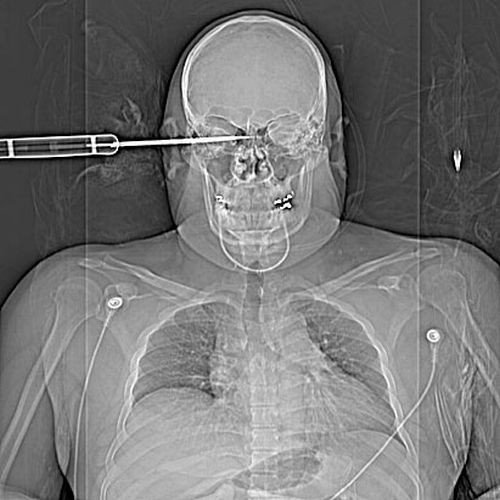

Radiografii terifiante: foarfece in cap, cuie in gat si furculite in mana

Surublenite infite in cap, plamani "dotati" cu cuie sau laringe "presarat" cu foarfece. Sunt numai cateva dintre cele mai ingrozitoare radiografii cu care s-au confruntat medicii de-a lungul timpului.

Iata mai jos o serie cu unele dintre cele mai "spectaculoase" radiografii.